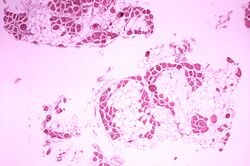

A cherry red spot, which can be a feature of several storage disorders, including Tay–Sachs disease